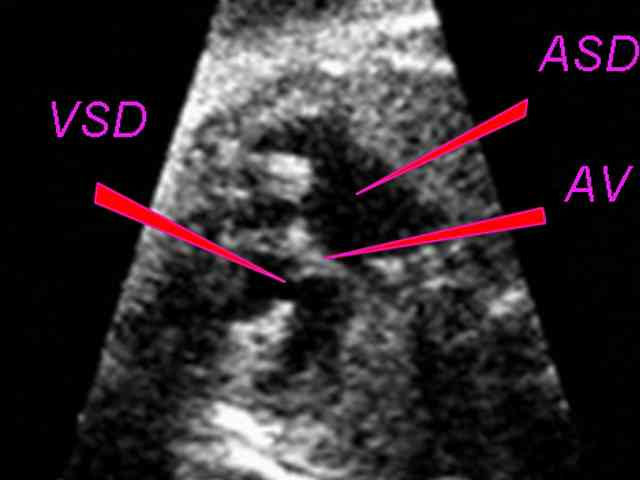

Дефект межжелудочковой перегородки (ДМЖП) самый частый ВПС. Встречается в 9-25% случаев.

В 2/3 случаев ДМЖП сочетается с другими ВПС.

Выделяют большой ДМЖП его величина сходна с диаметром аорты или превышает его, и небольшой или средних размеров меньше диаметра аорты, обычно 0,5-1,5 см.

Гемодинамика.

Артериальная кровь сбрасывается из левого в правый желудочек и легочную артерию, откуда возвращается в левые отделы сердца. Направление сброса обуславливается более высоким давлением в левом желудочке.

При диаметре дефекта 5 мм сброс равен 2,5-3 л/мин, а при диаметре 1,5-2 см 15-20 л/мин.